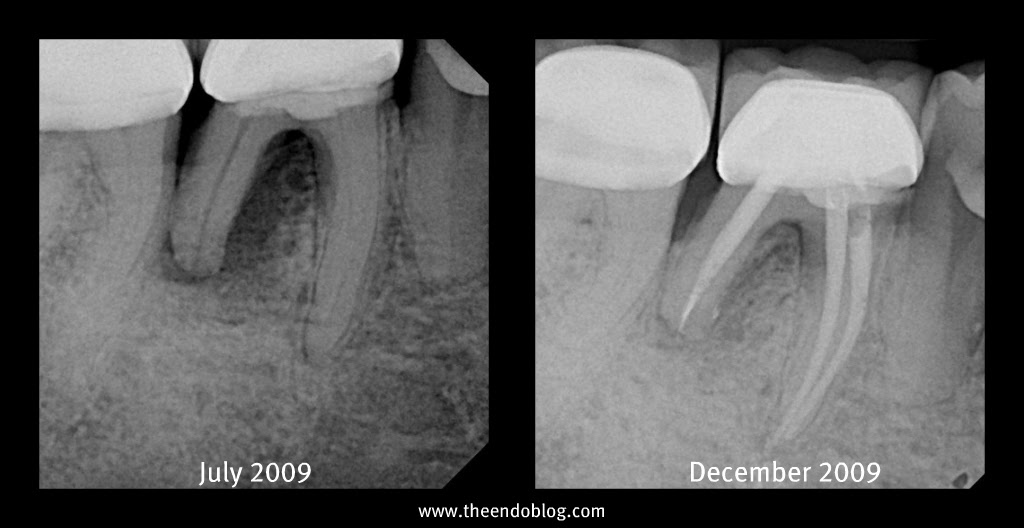

From www.theendoblog.com

The Endo Blog Diagnosing Root Fractures continued Vertical Root Fracture X Ray vertical root fracture is the most severe form of longitudinal tooth fracture, 1 which can cause an. The diagnosis of vertical root fracture can be problematic, and it often requires prediction rather than definitive identification. sir, precisely identifying vertical root fracture (vrf) in endodontically treated teeth is very challenging and can cause. in general, radiographic examination is. Vertical Root Fracture X Ray.

The Endo Blog Vertical Root Fracture Vertical Root Fracture X Ray this chapter will emphasize the importance of achieving an accurate and timely vertical root fracture diagnosis and will describe. the aim of this study was to evaluate the diagnostic accuracy of an optimised cbct protocol in the detection. vertical root fracture is defined as a longitudinally oriented fracture of the root, extending from the root canal. . Vertical Root Fracture X Ray.